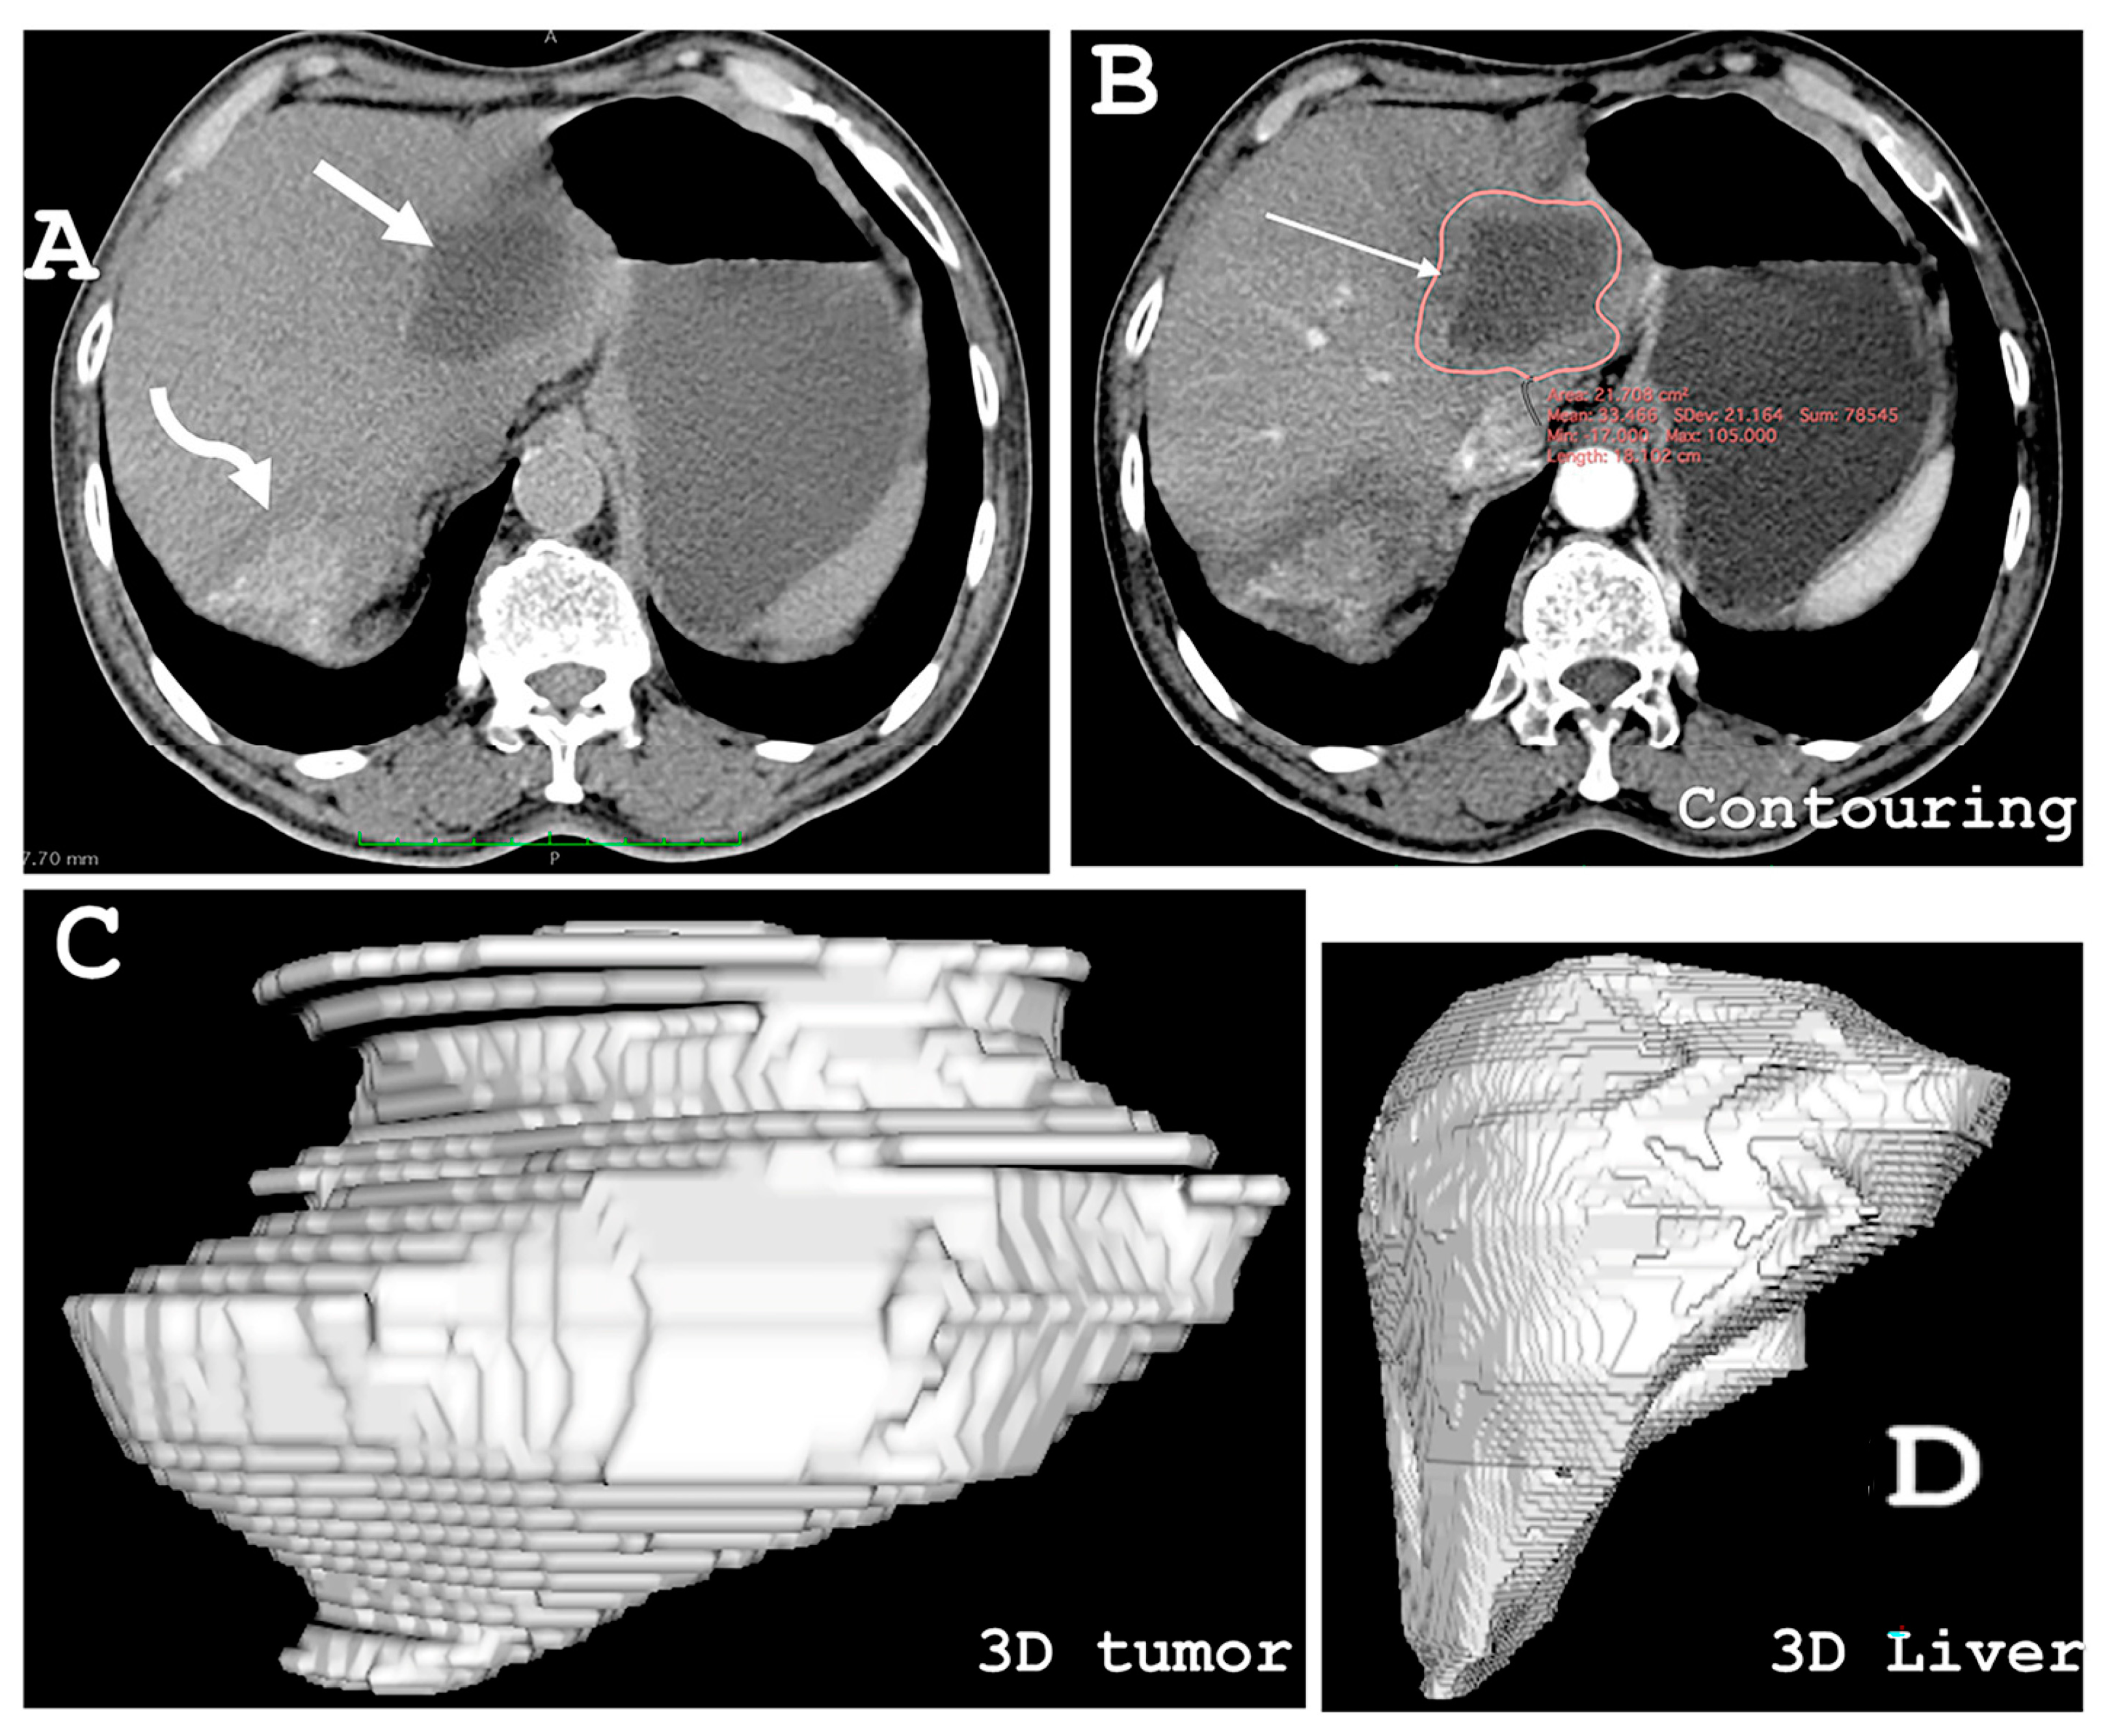

- Elsawaf, Y.; Anetsberger, S.; Luzzi, S.; Elbabaa, S.K. Three-Dimensional Volumetric Assessment of Resected Gliomas Assisted by Horos Imaging Software: Video Case Series of Postoperative Tumor Analyses. Cureus 2021, 13, e13571. [Google Scholar] [CrossRef]

- van der Vorst, J.R.; van Dam, R.M.; van Stiphout, R.S.; van den Broek, M.A.; Hollander, I.H.; Kessels, A.G.; Dejong, C.H. Virtual liver resection and volumetric analysis of the future liver remnant using open source image processing software. World J. Surg. 2010, 34, 2426–2433. [Google Scholar] [CrossRef] [PubMed]